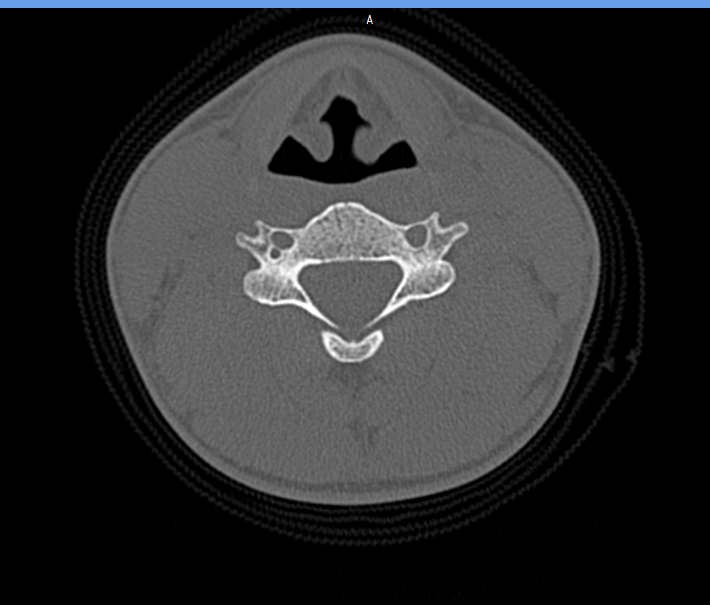

На снимках КТ хорошо визуализируются позвоночные суставы, суставные поверхности, межпозвонковые диски, которые часто подвержены дегенеративно-дистрофическим процессам. На томограммах также можно оценить состояние позвоночного канала, в котором располагается спинной мозг, выявить участки его сужения и предположить степень воздействия на спинномозговые структуры.

При обследовании шейного отдела позвоночника оценивается область основания черепа, семь шейных позвонков, верхние грудные позвонки. Помимо костных структур мультиспиральная КТ показывает состояние близлежащих органов и тканей: трахеи, пищевода, лимфатических узлов, кровеносных сосудов на исследуемом уровне.